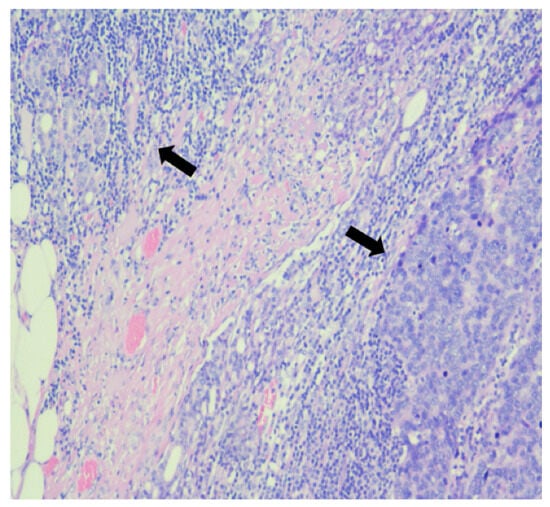

2. Case Report